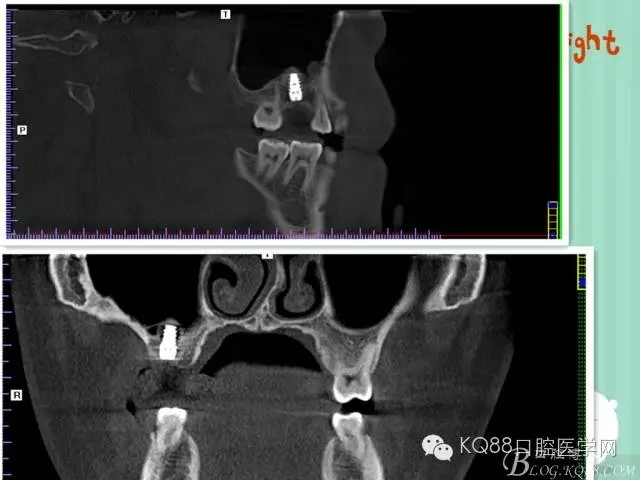

植入后,CBCT

另外一個(gè)切面。竇底粘膜完整連續(xù)??梢钥吹缴舷乱Ш系奈恢藐P(guān)系。

下面兩張是種植前后的對(duì)比片子。

手術(shù)前

手術(shù)后。